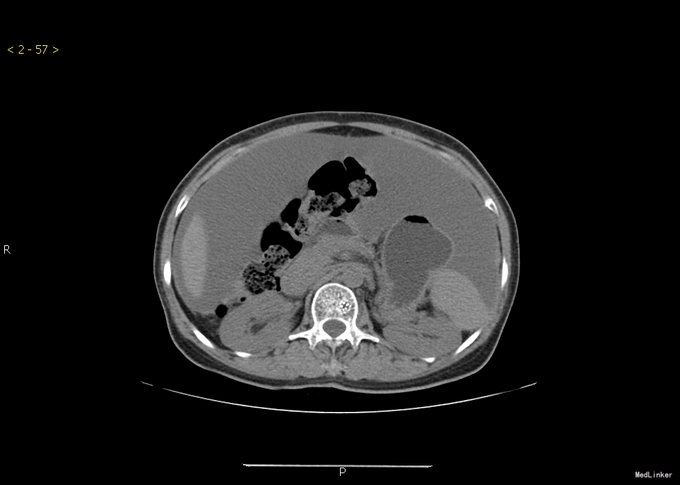

查体:腹部膨隆,腹部张力大,无压痛,无反跳痛,移动性浊音阳性。其余无特殊。 胸部+全腹部CT示:1.胸部增强扫描未见明确异常。2.盆腔底部腹膜明显不规则增厚,右侧附件可见肿块,考虑卵巢肿瘤可能。3.腹盆腔大量积液。

诊断:卵巢钎维瘤合并麦格综合征 治疗:行腹腔积液引流后,腹水未发现肿瘤细胞。后行全子宫双附件切除术。术后病理提示:卵巢纤维瘤。手术顺利。